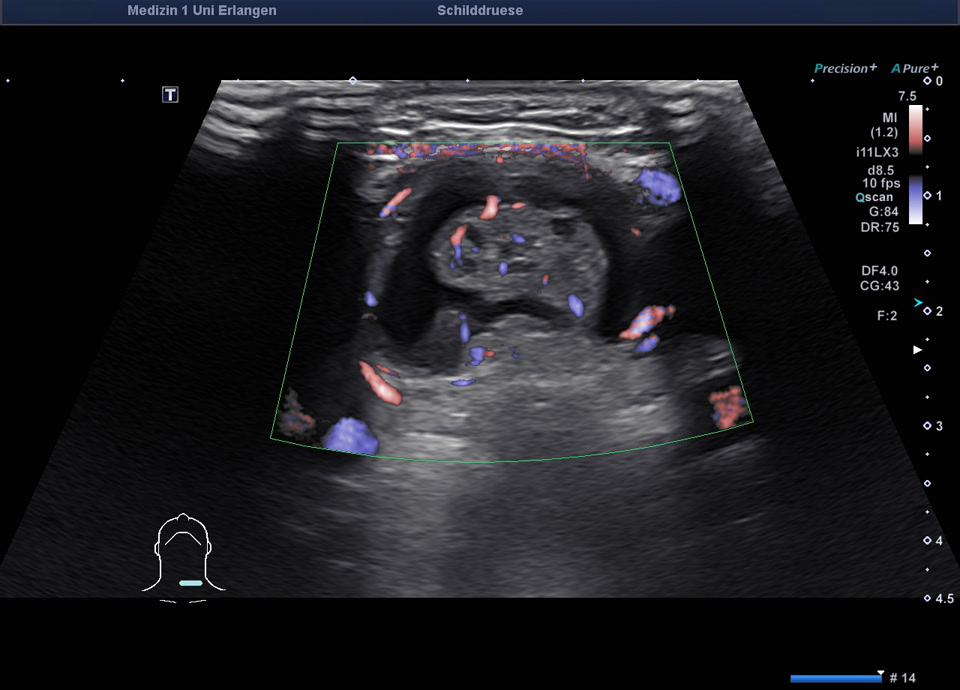

78-jähriger Patient mit Zufallsbefund einer hypodensen Schilddrüsenläsion im Rahmen eines Kardio-CTs vor geplanter Aortenklappenoperation. In der sonographischen Abklärung zeigte sich eine normal große Schilddrüse mit einem 2 cm echoarmen Knoten (EU-TIRADS 4), farbdopplersonographisch ohne relevante intranoduläre Durchblutung. Die Elastometrie zeigte eine erhöhte Gewebesteifigkeit. Der TSH-Wert lag im Normbereich, klinisch bestanden keine Hinweise auf eine Schilddrüsenerkrankung. Es erfolgte eine ultraschallgesteuerte Stanzbiopsie sowie eine Feinnadelpunktion mit zytologischer Aufarbeitung (Zytospin). Histologisch ergab sich ein follikulärer Knoten. Kommentar des Pathologen: anhand der Biopsie kann eine follikuläre Neoplasie nicht sicher von einem autonomen Adenom unterschieden werden. Zur funktionellen Abklärung (zum Nachweis eines autonomes Adenom) sollte eine Schilddrüsenszintigrafie erfolgen. Aufgrund der vorausgegangenen Kontrastmittelgabe (Kardio-CT) ist eine Schilddrüsenszintigrafie erst nach ≥8 Wochen möglich. Vorrangig erfolgt zunächst die Behandlung der hochgradigen Aortenstenose. Nach Durchführung der Szintigrafie ohne Nachweis eines Adenoms sollte aufgrund des Risikos einer follikulären Neoplasie eine operative Abklärung (diagnostische Hemithyreodektomie) erwogen werden. Alternativ sind sonographische Verlaufskontrollen nach 6 und 12 Monaten möglich.